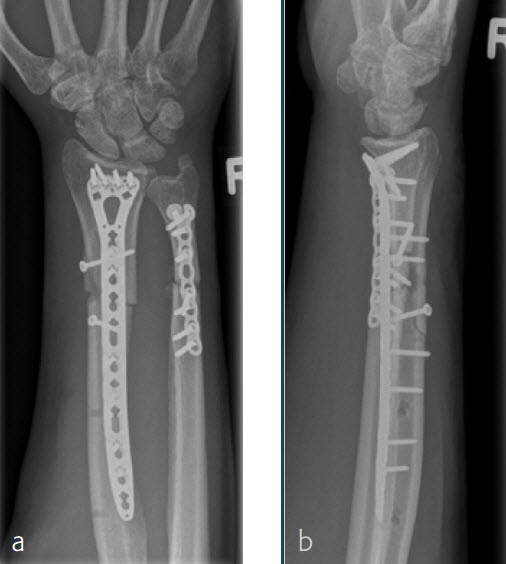

A 26-year-old man suffered a multifragmentary fracture of his left distal radius with extension into the diaphysis (AO23 C3.3) (Fig 1). The VA LCP Extra Long Two-Column plate was used for fixation (Fig 2). After initial immobilization, the plate provided a good postoperative fixation of the fracture.

The fracture showed primary bone healing without callus formation. At the 3-month follow-up, the patient was full weight bearing with excellent clinical function (Fig 3). The radiological follow-up can be technically challenging due to the correct focus of the central ray.